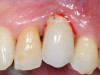

Fig 3. Peri-implant mucositis: mucosal inflammation.

Figure 3